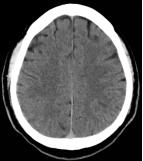

术前影像

图1急诊颅脑CT